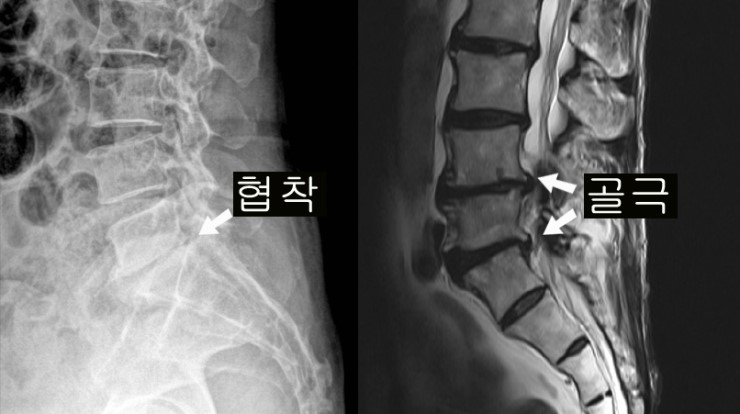

척추 관절과 인대가 변화되고 두꺼워져 척추 신경을 조이면 신경의 혈액순환이 부족하게 되어 발생합니다. 선천적으로 요추관의 크기가 정상보다 작게 만들어지는 경우로 대개는 35세가 넘어 뼈와 인대의 변화가 겹쳐서 증상이 발생되나 20세 전후의 아주 젊은 나이에도 간혹 발견되기도 합니다.

가장 흔한 원인으로 척추 퇴행성 골관절염이 생김에 따라 허리 관절의 크기가 커지고 인대도 두꺼워지는 동시에 가시 같은 뼈가 자라나 신경 길을 좁아지게 만듭니다.